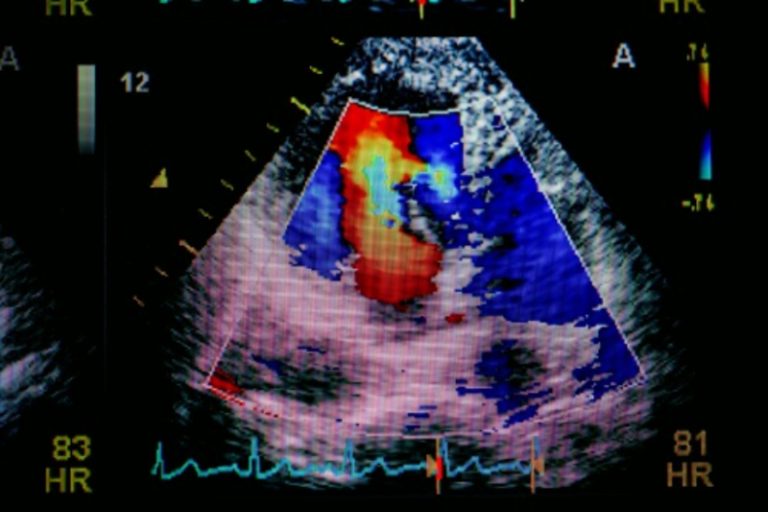

心臟病在香港最常見致命疾病中居第三位(頭兩名分別是癌症及肺炎),當中以冠心病(冠狀動脈心臟病)、心律不正、心瓣膜病、心臟衰竭為香港常見的心臟疾病。此文為大家詳細講解心臟檢查如靜臥/運動心電圖檢查、心臟超音波/超聲波檢查過程、心臟電腦掃描及其他心臟檢測,並為大家推薦7個心臟檢查及收費比較!